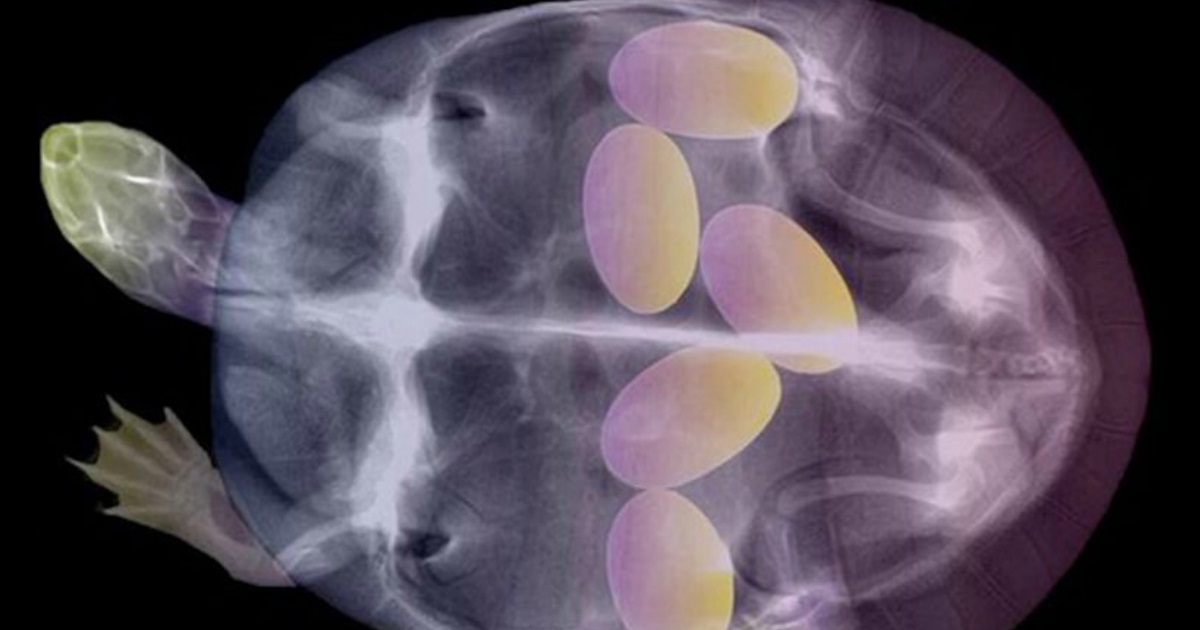

You'd be intrigued to know that medical physicist and photography enthusiast Arie van't Riet’s works feature close-up x-ray shots of pregnant animals so that you can witness the magic up close. In fact his X-ray photographs have often gone viral and he even has his own website. He specializes in radiation physics and is fascinated by black and white photography, which would make sense as to why he is so interested in x-rays. He has even insisted that he prefers observing x-rays of regular commonplace animals like butterflies and fish, and not just exotic animals. Here's having a good look at some of his artwork.